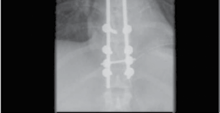

Figure 4.3 A fracture dislocation of the thoracic spine stabilised with posterior thoracic rods and screws.